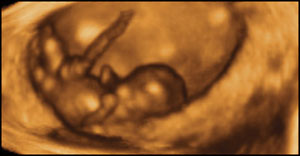

this is what an unborn baby looks like at 20 weeks (five months)